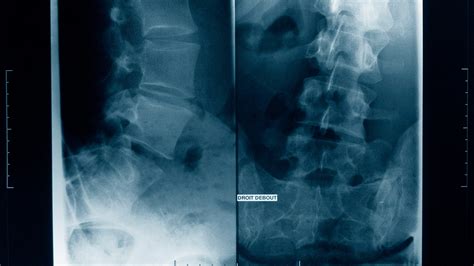

So, what is scoliosis, anyway? Imagine your spine as a straight, strong pole supporting your body. Now, picture that pole starting to bend to the side. That’s essentially what scoliosis is: a sideways curvature of the spine. But it’s not just a simple bend; it often involves a rotation, too. This means that the vertebrae (the individual bones of your spine) might twist on each other, which can lead to more complex issues. Scoliosis can range from mild to severe, and the impact it has on someone’s life varies depending on the severity of the curve and other factors. In general, a curve of 10 degrees or more is considered scoliosis. These curves are usually measured in degrees using the Cobb angle, a method used on X-rays to assess the severity of the spinal curvature. The curves typically develop in the upper back (thoracic spine), the lower back (lumbar spine), or both. Keep in mind that not all spinal curves are scoliosis; sometimes, the spine may appear curved due to poor posture or other temporary factors. Therefore, proper diagnosis by a healthcare professional is crucial. Understanding the basics helps pave the way to addressing and managing the issue effectively, from the early stages to the need for more complex treatments. So, whether you are here to learn more about the condition or you are just curious, welcome!

So, how do doctors diagnose scoliosis ? The diagnosis process typically begins with a physical examination. The doctor will visually assess the person’s posture, looking for any signs of unevenness in the shoulders, waist, or hips. They might also perform the Adam’s forward bend test to check for a curve in the spine. If scoliosis is suspected, the next step is usually an X-ray. X-rays can confirm the presence and severity of the spinal curvature. The Cobb angle, mentioned earlier, is measured on the X-ray to determine the degree of the curve. This measurement is crucial for guiding treatment decisions. In some cases, additional imaging tests might be needed. This might include MRI scans or CT scans, particularly if the doctor suspects an underlying cause for the scoliosis, such as a tumor or neurological issue. These advanced imaging techniques can provide detailed information about the spine and surrounding tissues. Once the X-rays or other imaging is completed, the doctor will take the time to evaluate the results, discuss them, and provide you with a diagnosis and recommend the appropriate treatment plan. The diagnosis can involve collaboration with other healthcare professionals, like physical therapists or orthopedists. Getting an accurate diagnosis involves a thorough assessment, from a physical examination to imaging tests. This detailed approach is designed to ensure an accurate understanding of the condition and the development of an effective management strategy.